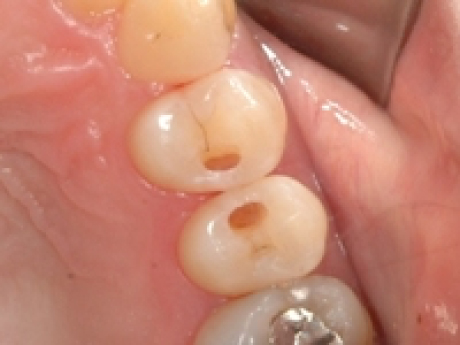

case1